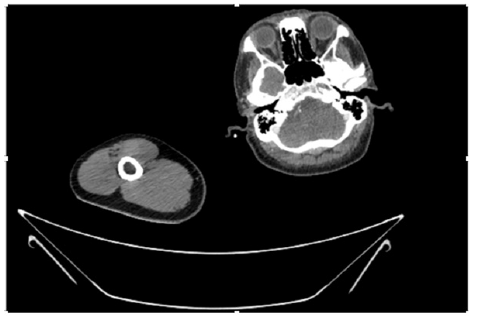

55-years-old chronic smoker had acute, severe pain in the right upper limb for one week; it was cold upto mid arm with skin discoloration. He also noticed numbness and weakness of movement of elbow joint. He underwent below elbow amputation in February 2023 for acute ischemia of left upper limb. He was a current chronic smoker; 15 pack year. General condition was weak; temperature was normal; blood pressure was 100/60mmHg; heart rate was 92/minutes with sinus rhythm; SpO2 was 97% on air; heart was normal. In lower extremities, all peripheral pulses were intact. Local Examination of right upper limb revealed as follows: tenderness; coldness; discoloration; decreased motor function and sensory modalities. Axillary, brachial and radial pulses were not palpable. Hand-held Doppler failed to detect any signal in arterial system; therefore, we arranged for emergency embolectomy. complete occlusion of right upper limb arterial system Full blood count showed high hemoglobin (14.6gm%); normal total WBC and platelet count. Coagulation profile was normal. Parenteral unfractionated heparin, antibiotics, tramadol, proton-pump inhibitors, anti-platelets and HMG CoA reductase inhibitors were given. Doppler ultrasound demonstrated complete occlusion of right upper limb arterial system. CT Angiogram illustrated occlusion of subclavian artery downwards on both sides. Figures 1-14 shows complete occlusion of right subclavian artery without collaterals. On Day ‘2’ of admission, the patient passed black tarry stool for 3 times. However, the vital signs were stable; blood pressure was 100/60mmHg; heart rate was 92/min; SpO2 was 97% on air; the abdomen was soft and not tender. Above elbow amputation was done on Day ‘2’ of admission. Intra-operative findings were as follows: (1) no active bleeding at brachial artery; (2) thrombosis along brachial artery; (3) muscle color and consistency were not healthy.

Figure 4: CT Angiogram at neck showing normal brachio-cephalic trunk, common carotid artery, and narrow right subclavian artery.

Figure 5: CT Angiogram at neck showing normal brachio-cephalic trunk, common carotid artery, and narrow right subclavian artery.

Figure 6: CT Angiogram at neck showing brachio-cephalic trunk, common carotid artery and narrow right subclavian artery.

Figure 7: CT Angiogram at neck showing brachio-cephalic trunk, common carotid artery and narrow right subclavian artery.

Figure 10: CT Angiogram at upper arm showing totally occluded right axillary artery; normal internal carotid artery and external carotid artery.